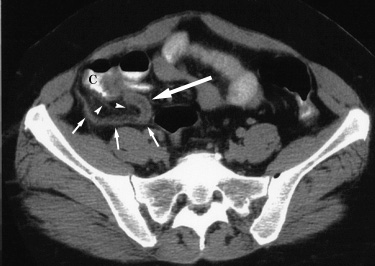

| Nonperforated appendicitis. 16 year old girl with focal pain, right lower quadrant tenderness, and fever for two days. A CT examination was obtained to evaluate for appendicitis, shown below. |

An axial CT image in the upper pelvis shows edema of the cecal wall which, along with barium in the cecum (C), contributes to the "arrowhead sign" of appendicitis. A dilated fluid filled appendix (large arrow) is seen with adjacent stranding of retroperitoneal fat (arrowheads). The appendix follows a retrocecal course (small arrows). |

| At surgery a nonperforated inflamed appendix was removed. |